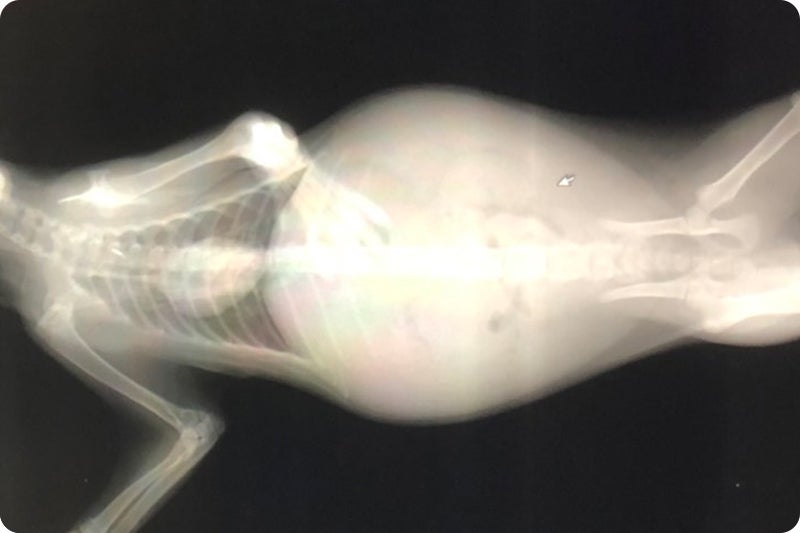

毎日病院で点滴を受け血液検査、レントゲン、エコー、注射を繰り返す日々。

キティの場合ウェットタイプです。

腹水が貯まりパンパンになりました。

9月7日(月) 病院Aにてレントゲン、エコー